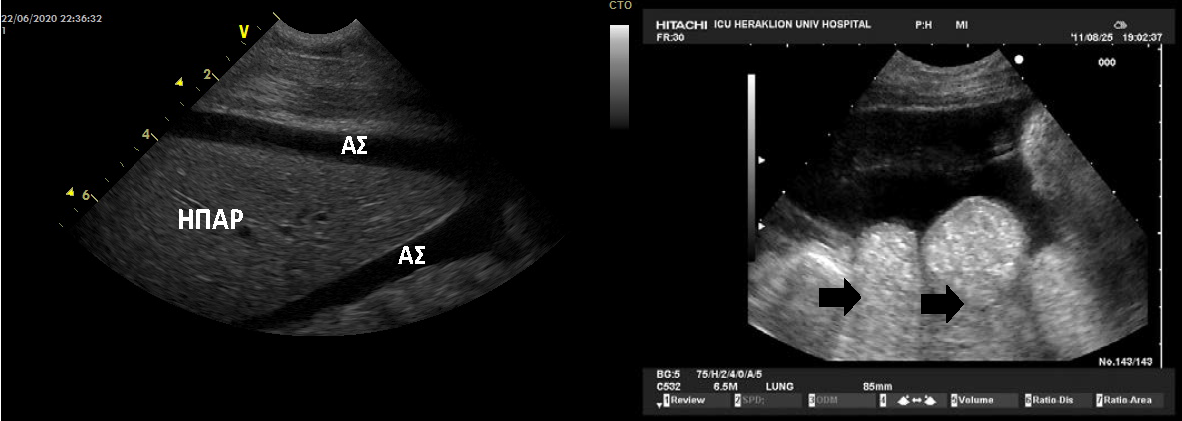

περιπτώσεις η μέτρηση της κεντρικής φλεβικής πίεσης είναι αναξιόπιστη.[23] Εικ. 5. Αναπνευστική ανεπάρκεια

σε έδαφος πνευμονικού οιδήματος. Α. Υπεζωκοτική συλλογή (ΥΣ),

ατελεκτασία κάτω λοβού (Α), ειπλέων πνεύμονας, ομαλά όρια διαφράγματος (Δ).

Β. Πολλαπλές Β-γραμμές – white lung (βέλος) Γ. Σαφή ομαλά όρια ημιδιαφράγματος (βέλος) Δ.

Υπεζωκοτική συλλογή (ΥΣ),

ημιδιάφραγμα (βέλος). Ε. Παραστερνική κατά το βραχύ άξονα της

ΑΡ κοιλίας Ζ. Ατελεκτασία ετέρου κάτω λοβού (Α) με επιπλέοντα

πνεύμονα και σαφή όρια ημιδιαφράγματος και ΥΣ. Η. Κάτω κοίλη φλέβα.

αγγειακό σύστημα, μειώνοντας έτσι σημαντικά την πιθανότητα επιπλοκών. (Εικ. 12) Εικ.12

Ασκιτική συλλογή (ΑΣ) γύρω από το ήπαρ και ανάμεσα στις εντερικές έλικες.